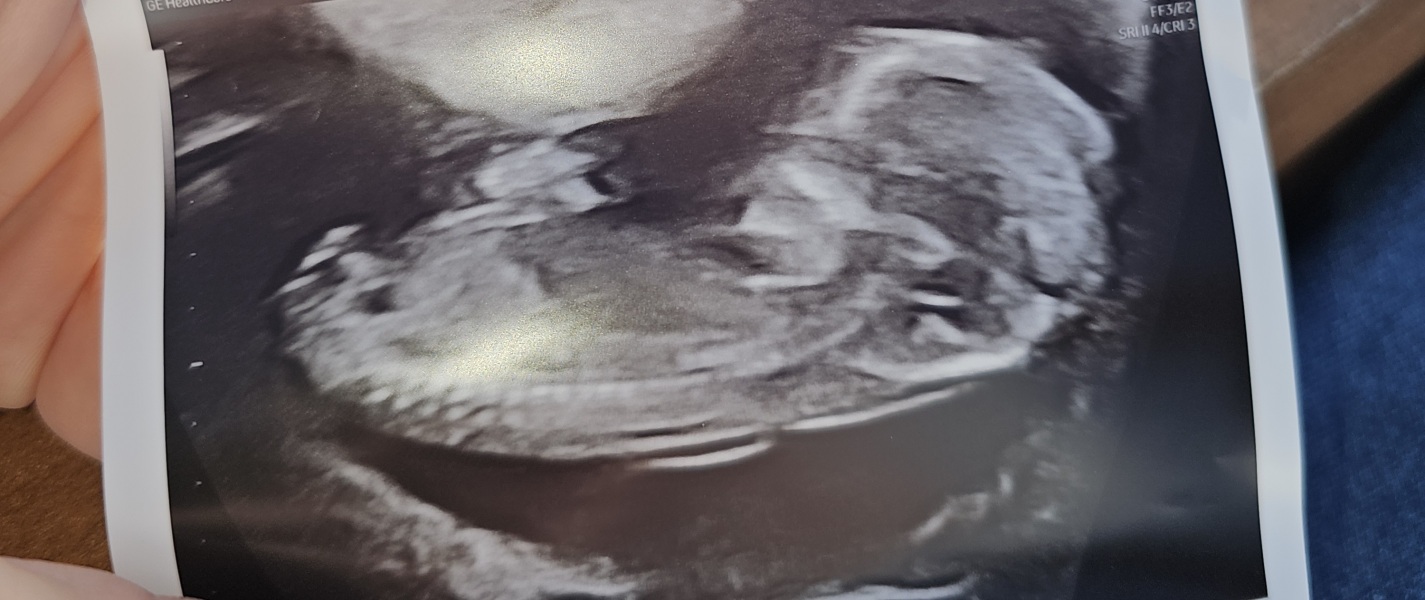

Jadeypie · 02/07/2025 17:47

Scan went perfect. Due date come forward to the 1st xx

Ahhh love this @Jadeypie whats your thoughts on gender lol x

Im saying boy. Hahah xx

Im also going with boy 💙xx